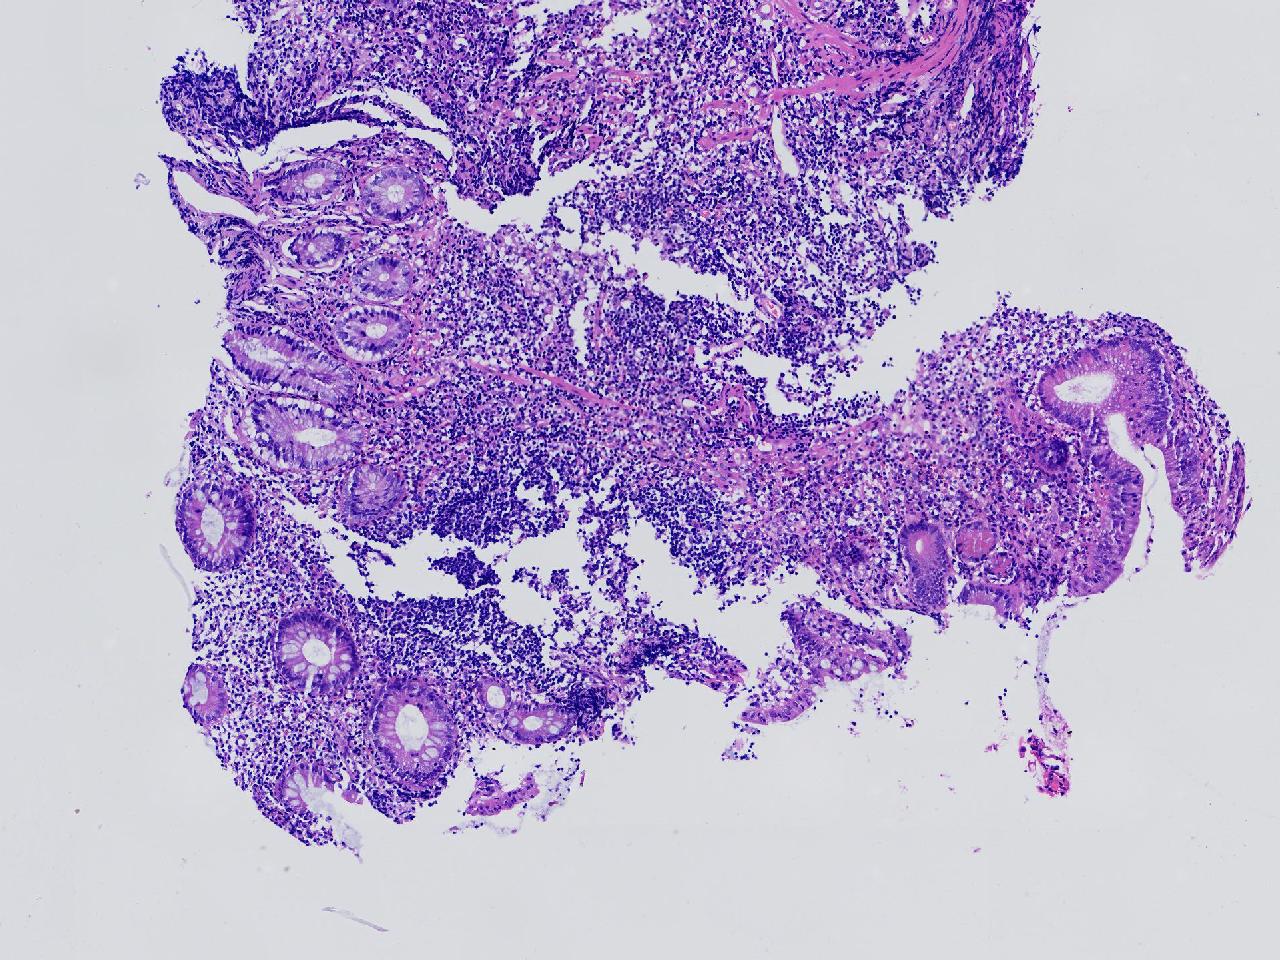

男,62岁,回盲部附近见多发片状溃疡,底覆薄白苔,周围粘膜充血水肿,活检2块,质软,弹性可。

回盲部活检

灰白色不整形软组织2块,直径均0.2厘米。

考虑:溃疡性结肠炎?

炎症性肠病要考虑,具体的类型不太好确定,需要结合临床。

上级医院会诊,不除外炎症性肠病,结合临床。